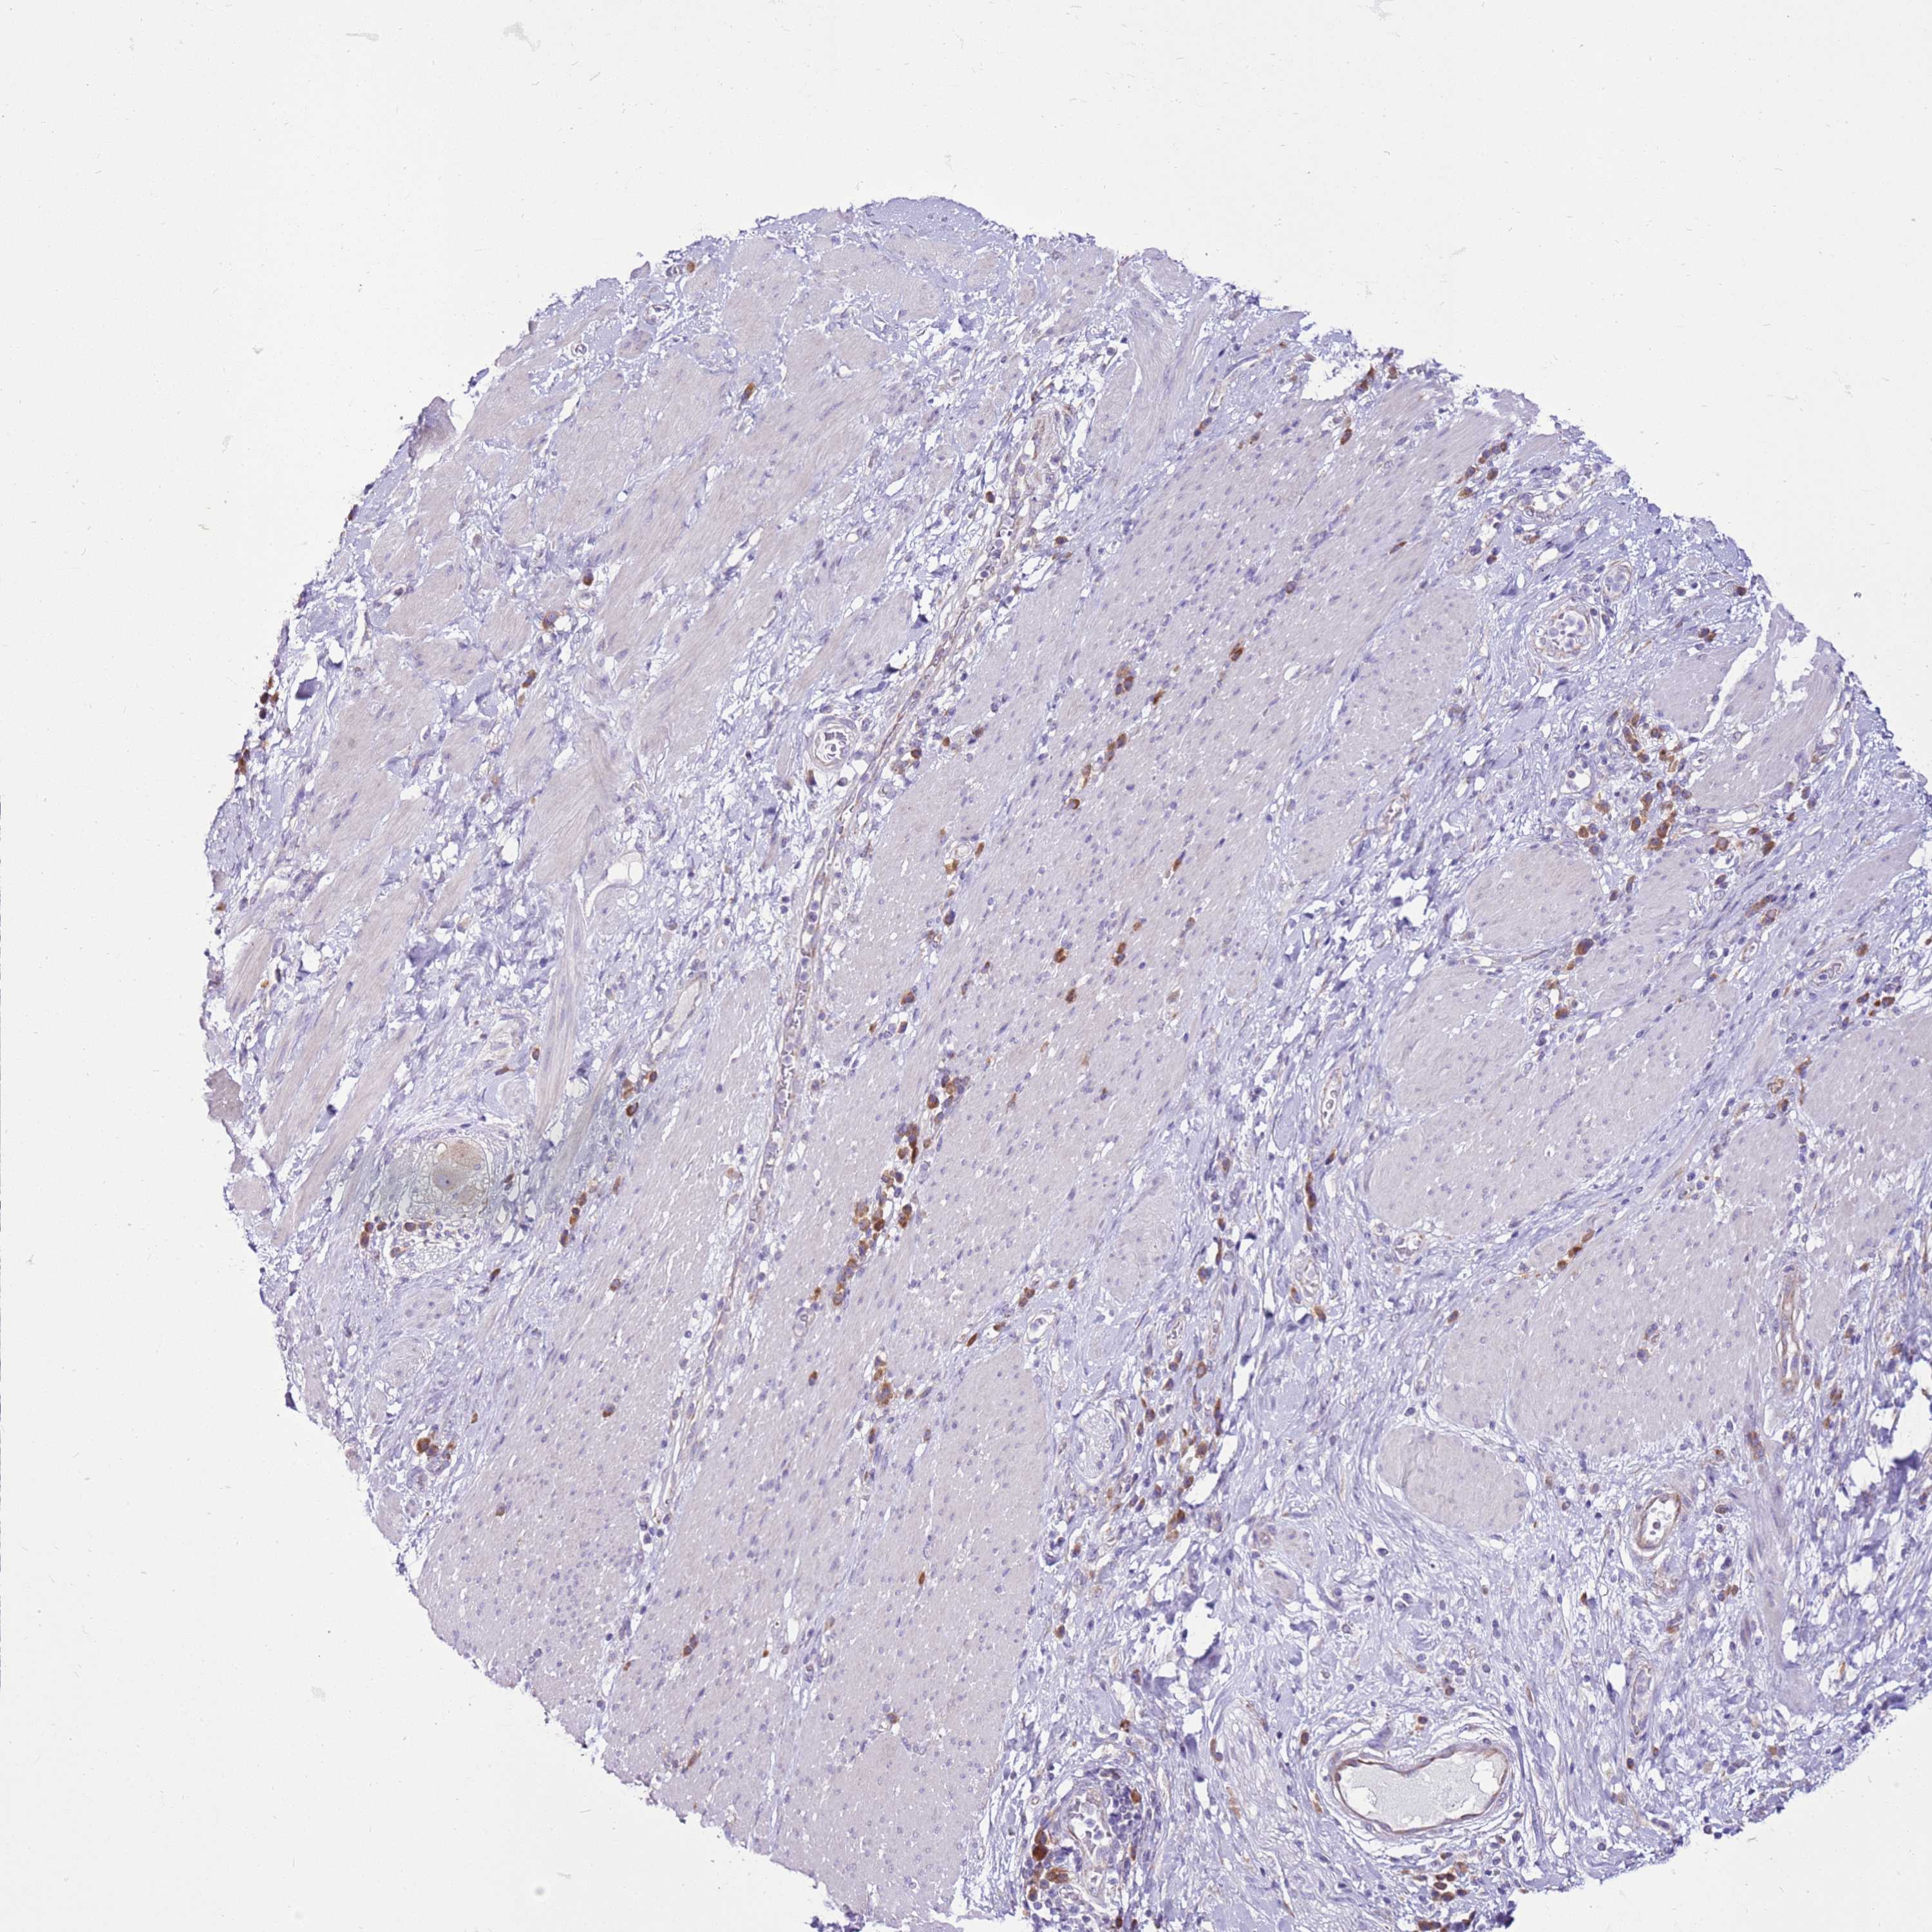

STOMACH CANCER - Protein expressioni

A mouse-over function shows sample information and annotation data. Click on an image to view it in a full screen mode. Samples can be filtered based on level of antibody staining by selecting one or several of the following categories: high, medium, low and not detected. The assay and annotation is described here.

Note that samples used for immunohistochemistry by the Human Protein Atlas do not correspond to samples in the TCGA dataset.

Antibody stainingi

Antibody staining in the annotated cell types in the current human tissue is reported as not detected, low, medium, or high, based on conventional immunohistochemistry profiling in selected tissues. This score is based on the combination of the staining intensity and fraction of stained cells.

Each image is clickable and will lead to virtual microscopy that enables deeper exploration of all samples and also displays staining intensity scores, fraction scores and subcellular localization as well as patient and tissue information for each sample.

Antibody HPA047238

Staining

High

Medium

Low

Not detected

Intensity

Strong

Moderate

Weak

Negative

Quantity

>75%

75%-25%

<25%

None

Location

Nuclear

Cytoplasmic/membranous

Cytoplasmic/membranous,nuclear

Adenocarcinoma, NOS